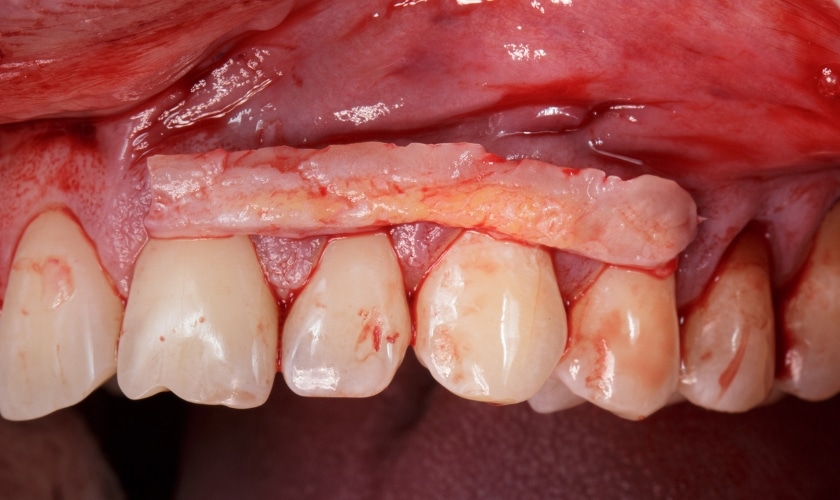

- Free gingival graft: This technique involves taking a small piece of tissue from the palate and placing it over the receded area.

- Connective tissue graft: This method uses tissue from under the palate, providing additional support for the gums.

- Pedicle graft: This technique utilizes neighboring gum tissue, creating a flap that is rotated to cover the exposed root surface.